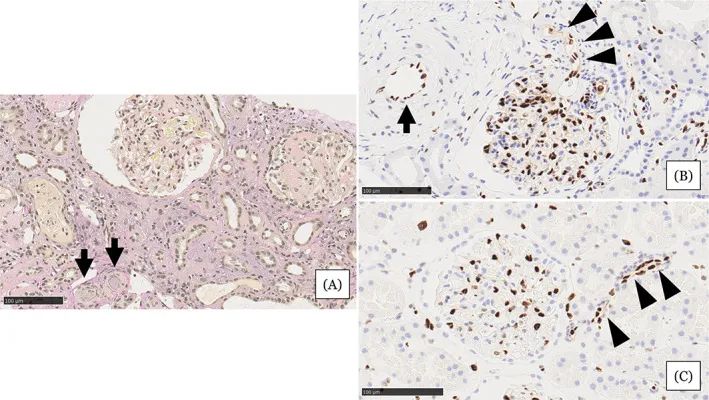

在住院第31天進行的腎活檢結(jié)果

圖注:在住院第31天進行的腎活檢結(jié)果。A,顯示小動脈被粘液性內(nèi)膜增厚(箭頭)堵塞,腎小球萎縮,毛細血管壁起皺,嚴重的間質(zhì)單核細胞浸潤伴腎小管損傷。B,EC細胞核的缺乏在小動脈(箭頭)中很突出。在相鄰的小動脈(箭頭)中注意到不同大小的不規(guī)則細胞核。C,EC的等距核在血壓正常的腎臟供體的腎臟小動脈中形成有序的線。比例尺 =100μm